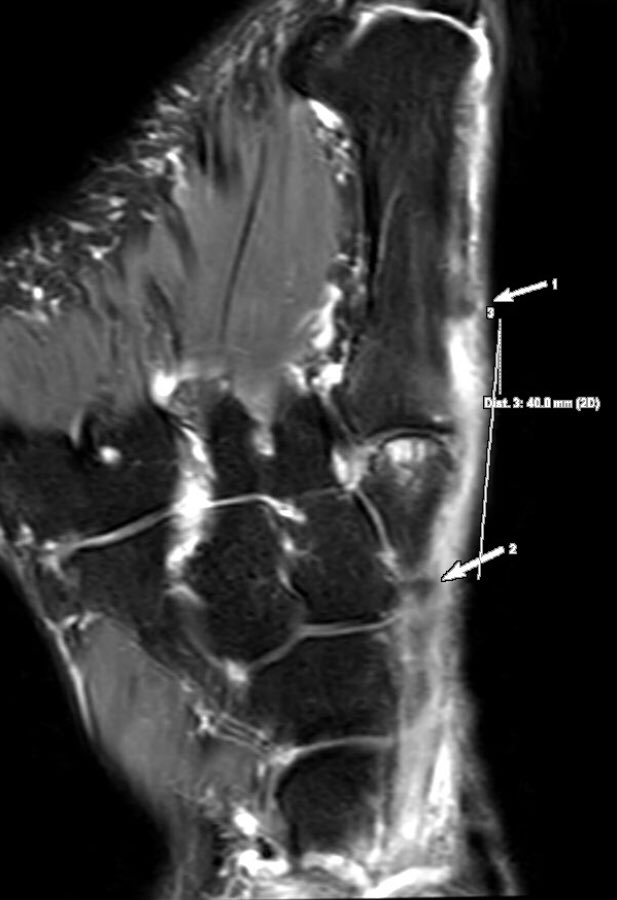

Extensor hallucis longus (EHL) tendon closed full-thickness tear: fluid inside tendon sheath, abrupt EHL tendon fibers complete discontinuity with a 4-cm gap, tendinopathy of both stumps. Mechanical impingement by bone spurs.

#MSKrad#foot#orthopaedicspic.twitter.com/h9LcB2Pgjp